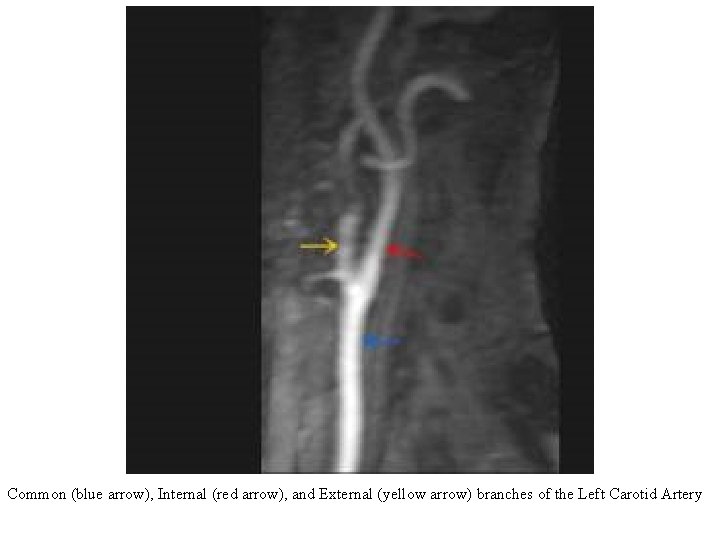

Common (blue arrow), Internal (red arrow), and External (yellow arrow) branches of the Left Carotid Artery